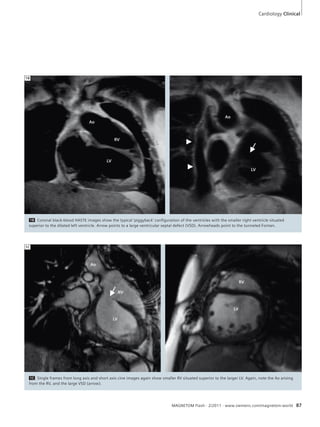

Clinical Cardiology

84 Pediatric Congenital Heart MR

Imaging at 3T and 1.5T Systems

Pamela K. Woodard, et al.